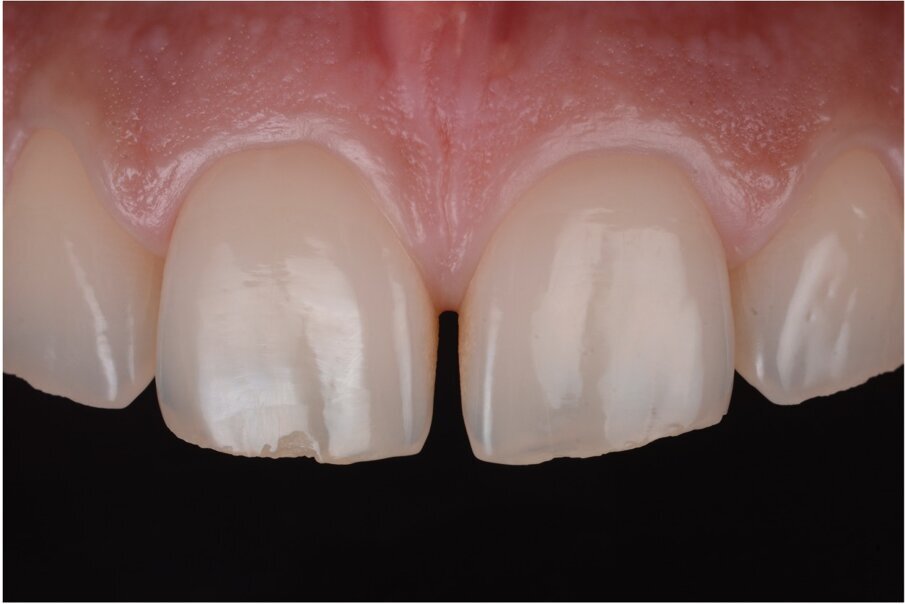

Fig. 2–4: Common troubles with a classic approach.

What were the associated problems with the older techniques including the one you used? The greatest problem for the freehand techniques, without a doubt, is the lack of cervical precision and the creation of overhangs. I have seen countless patients with bleeding gums that are not able to floss properly. Another common problem with the classical approach was the final shape. With a double emergence profile, it gave the final restoration an awkward shape (Figs. 2–4). Problems for direct diastema closure exclusively with matrices are the over contouring and the under contouring at the cervical level, discordant contact points, shifted proximal contacts, and massive excess production. To be honest, I have always been discouraged from trying that approach.